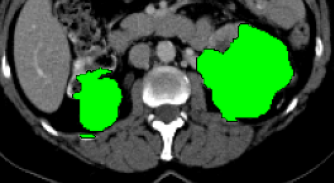

Current research on deep learning for medical image segmentation exposes their limitations in learning either global semantic information or local contextual information. To tackle these issues, a novel network named SegTransVAE is proposed in this paper. SegTransVAE is built upon encoder-decoder architecture, exploiting transformer with the variational autoencoder (VAE) branch to the network to reconstruct the input images jointly with segmentation. To the best of our knowledge, this is the first method combining the success of CNN, transformer, and VAE. Evaluation on various recently introduced datasets shows that SegTransVAE outperforms previous methods in Dice Score and $95\%$-Haudorff Distance while having comparable inference time to a simple CNN-based architecture network. The source code is available at: https://github.com/itruonghai/SegTransVAE.